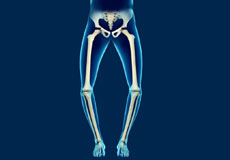

Blount's Disease

Blount’s disease, also known as tibia vara, is a developmental growth abnormality that affects the growth plate of the shin bone (tibia), causing the lower leg to angle outwards with a bow-like appearance.